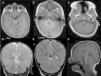

RS parcial aislada. A-C) Axial SPGR T1 de rostral a caudal: mesencéfalo (A), protuberancia (B) y unión bulbo-medular (C). Nótese la presencia de la porción anterior del vermis (A), la fusión caudal del vermis posterior (B) y la fusión rostral y posterior de los hemisferios cerebelosos con disposición horizontal de las folias (C). D-E). Coronal FSE T2. Ausencia de la porción inferior del vermis posterior; obsérvense la língula en el vermis anterior (D) y la fusión de los hemisferios cerebelosos con continuidad de las folias y sustancia blanca cruzando la línea media F) Sagital medio FLAIR T1. Nódulo presente.

Recién nacido a término, varón, primer hijo de padres sanos, no consanguíneos, que ingresa por sospecha prenatal de hipoplasia cerebelosa. Sin incidencias en el periodo perinatal. En el examen físico neonatal destacan una implantación baja de orejas, hipertelorismo e hipotonía generalizada. La ecografía trasfontanelar no identificó alteraciones de la fosa posterior. En la valoración del 5.° mes de vida presenta dificultad para mantener el sostén cefálico e iniciar sedestación en trípode, los rasgos faciales dismórficos descritos, objetivándose además un estrabismo convergente de ambos ojos. Adecuado crecimiento cefálico. Se realizó una RM cerebral que mostró una rombencefalosinapsis (RS) parcial aislada (fig. 1).

Su diagnóstico con RM no es difícil: en los planos coronales y axiales se aprecia la fusión de los hemisferios cerebelosos con disposición horizontal y continuidad de las folias en la línea media, y ausencia parcial o total del vermis. En el plano sagital medio puede sospecharse por la ausencia de la fisura primaria y prepiramidal4.